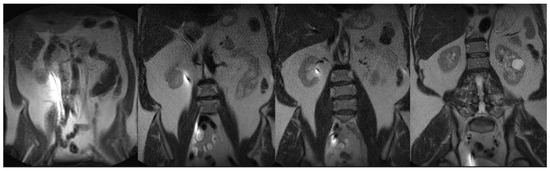

2. Methods

2.3. Ureteral Stent Placement Procedure